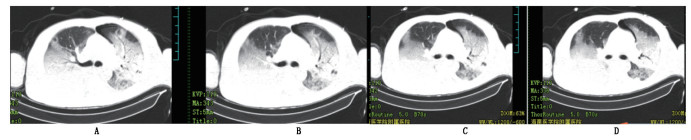

图 1 2016年11月4日床旁胸片提示双侧肺多发炎症,未见有气胸影。 |

患者男,37岁,因“发热4天,胸闷、气促伴呕吐1天”于2016年11月01日入院,4天前受凉后出现发热,最高体温达39.8℃。外院诊断“社区获得性肺炎”,予“阿奇霉素”抗感染及“布洛芬”解热等治疗。治疗后症状未见明显缓解。既往有2型糖尿病10余年,不规律口服降糖药及胰岛素治疗,未监测血糖,己自行停药约7年。入院查体:T 38.9℃,P 117次/min,R 20次/min,BP 138/85 mmHg。神清,精神疲倦。双肺呼吸音粗,右肺可闻及少许湿罗音。左侧腹股沟可见1 cm×2 cm的皮肤破溃,有脓性分泌物(患者诉2016年10月18日台风“莎莉嘉”后无明显诱因出现腹股沟区皮肤破溃)。入院辅助检查:床旁查末梢血糖提示高测不出;血常规示WBC 15.27×109/L,NEUT 88.8%;CRP:83.56 mg/L;PCT:1.36nE/mL;细菌内毒素0.2289EU/mL,1-3-β-D 364.6435;血气分析:PH 7.173,PCO2 2.04 Kpa,PO2 13.014 Kpa,AB 3.3 mmol/L,BE-20.9 mmol/L;血生化:葡萄糖28.75 mmol/L,Na+ 124.0 mmol/L,CL- 89.5 mmol/L;β-羟丁酸5.82 mmol/L,肝肾功能未见明显异常;糖化血红蛋白14.1%;C肽0.18ng/mL;抗人胰岛素抗体末见异常;尿液分析:尿糖(++++),尿蛋白(+),尿酮(++++)。余检查如传染病筛查、甲状腺功能五项、肿瘤指标等未见异常;心电图示:①窦性心动过速(114 bpm);②ST-T异常改变;2016年10月30日外院胸部CT示:右肺下叶少量渗出影。床旁胸片提示双侧肺多发炎症,未见有气胸影(图 1)。初步诊断:1.肺部感染;2.糖尿病酮症酸中毒;3.低钠血症;4.左侧腹股沟皮下脓肿。治疗经过:治疗上予哌拉西林/他唑巴坦抗感染、